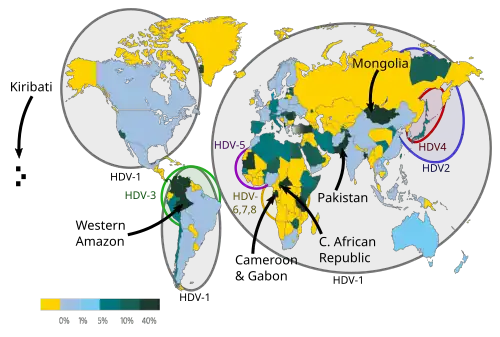

Hepatitis D

The hepatitis D virus causes chronic and fulminant hepatitis in the context of co-infection with the hepatitis B virus.[107] It is primarily transmitted via non-sexual contact and via needles.[18][107] Susceptibility to hepatitis D differs by geographic region.[18][107] In the United States and Northern Europe, populations at risk are intravenous drug users and people who receive multiple transfusions.[18][107] In the Mediterranean, hepatitis D is predominant among hepatitis B virus co-infected people.[18][107]